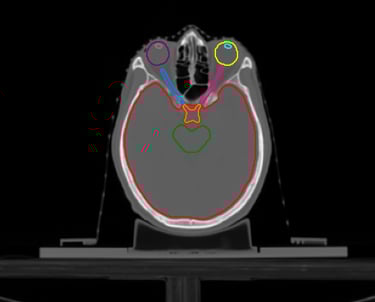

O SegmentaR foca na segmentação automática das três regiões fundamentais para o planejamento de radioterapia: cabeça e pescoço, tórax e pelve. Essas são as regiões essenciais que todo profissional precisa para uma segmentação precisa e eficiente.

Cabeça e Pescoço

Mandíbula

Cérebro

Tronco Cerebral

Cavidade Oral

Cóclea Esquerda

Cóclea Direita

Esôfago

Olho Direito

Olho Esquerdo

Glândula Tireoide

Laringe

Cristalino Direito

Cristalino Esquerdo

Quiasma Óptico

Nervo Óptico Esquerdo

Nervo Óptico Direito

Parótida Esquerda

Parótida Direita

Medula Espinhal